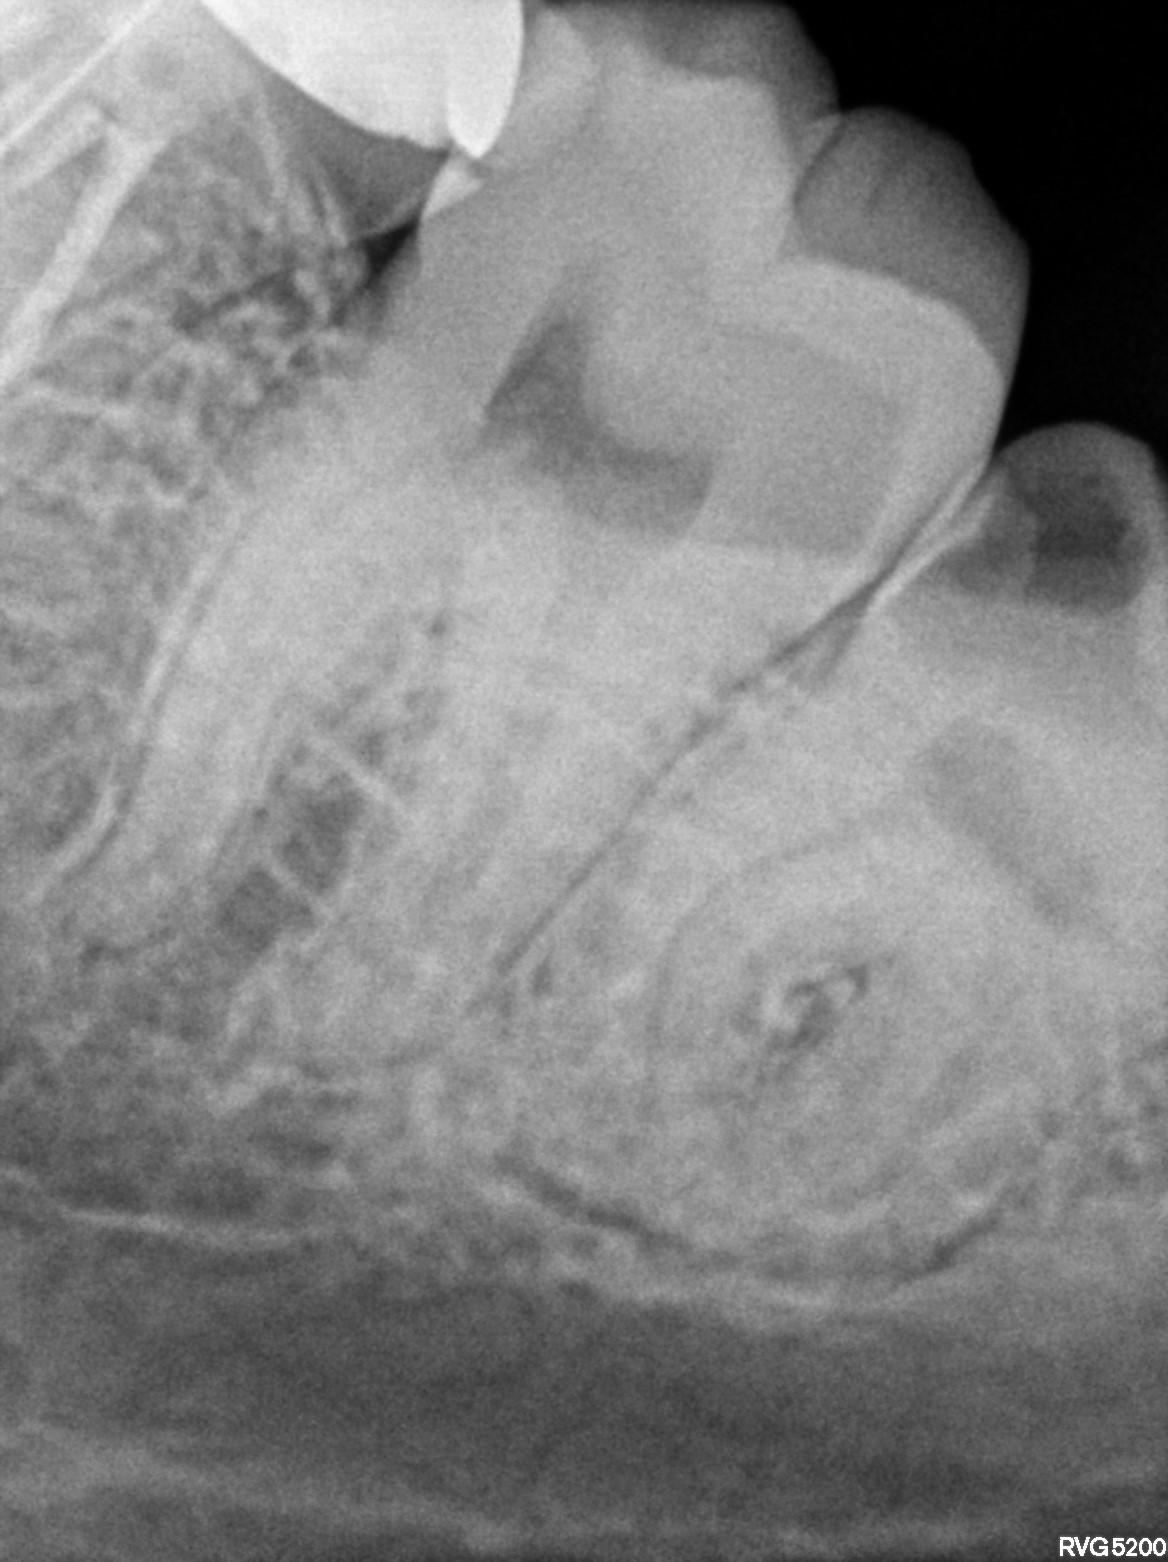

Dental Radiographs FHIR: DocumentReference · LOINC 24641-7

xray_1772899428_0.jpg

24641-7

| Necrosis of dental pulp | K04.1 | 234946006 | resolved | 2026-03-07 | adv rct with 47(5k-5500) followed by ceramic crown 3500 and surgical extn with 38 @7k-8k// extn with 48 advised only if pain persists and if pt wills | |

| Root canal treatment | 234780006 | D3330 Endodontic therapy, molar tooth | ##47, #38, #48 | 2026-03-07 | completed | adv rct with 47(5k-5500) followed by ceramic crown 3500 and surgical extn with 38 @7k-8k// extn with 48 advised only if pain persists and if pt wills | |

| 2026-03-07 21:33 | fulfilled | adv rct with 47(5k-5500) followed by ceramic crown 3500 and surgical extn with 38 @7k-8k// extn with — Dr Hani | |